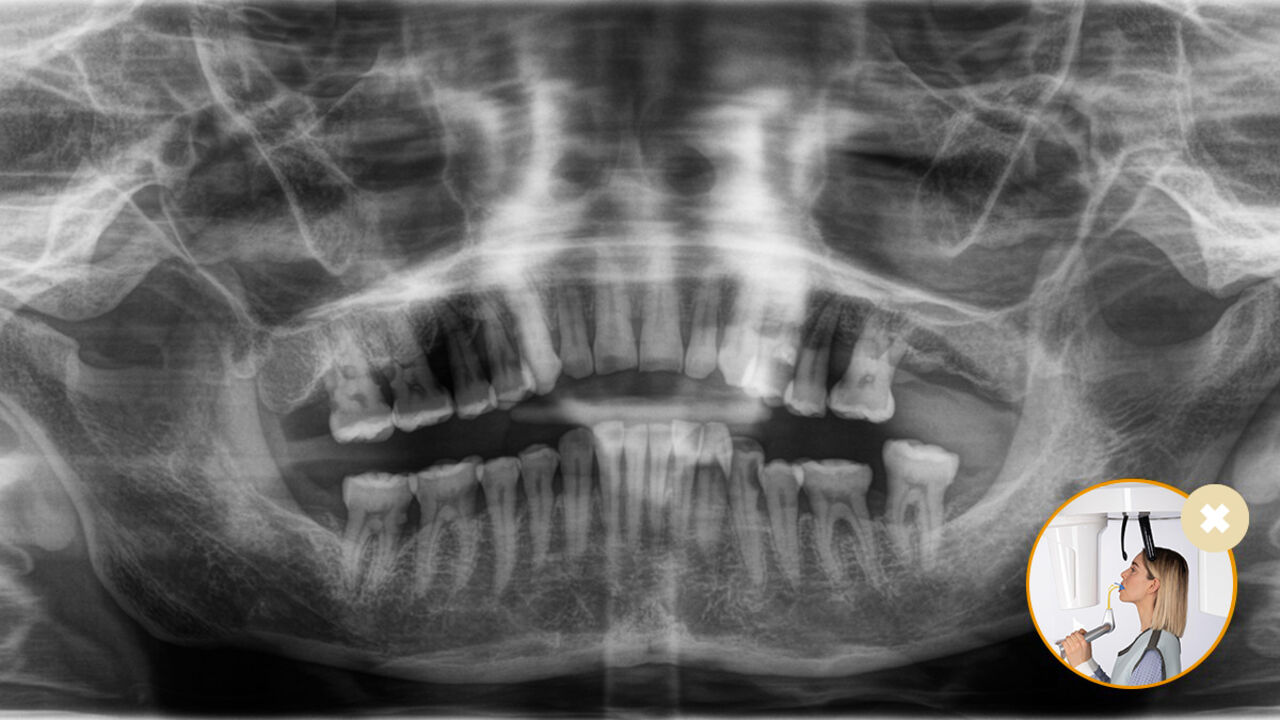

Die korrekte Patientenpositionierung führt zu einer hohen Bildqualität, die eine genaue Diagnose ermöglicht und die Patientenerfahrung erleichtert und verbessert.

Dies ist unser 10-Punkte-Konzept für die einfache Patientenpositionierung und Röntgenbildgebung. Es geht in erster Linie um zwei Dinge: Hochwertige Aufnahme und Komfort für den Patienten und die Assistenten.

Das Ergebnis: Präzise Scans dank des Okkusalaufbisses